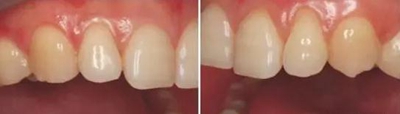

上下前牙側(cè)面影像

頭部向非拍攝側(cè)轉(zhuǎn)45°角

使側(cè)切牙、尖牙及雙尖牙暴露在照片中心

拍攝比例:1:1.8,光圈f38-45,快門速度1/125-180,閃光強(qiáng)度M/4